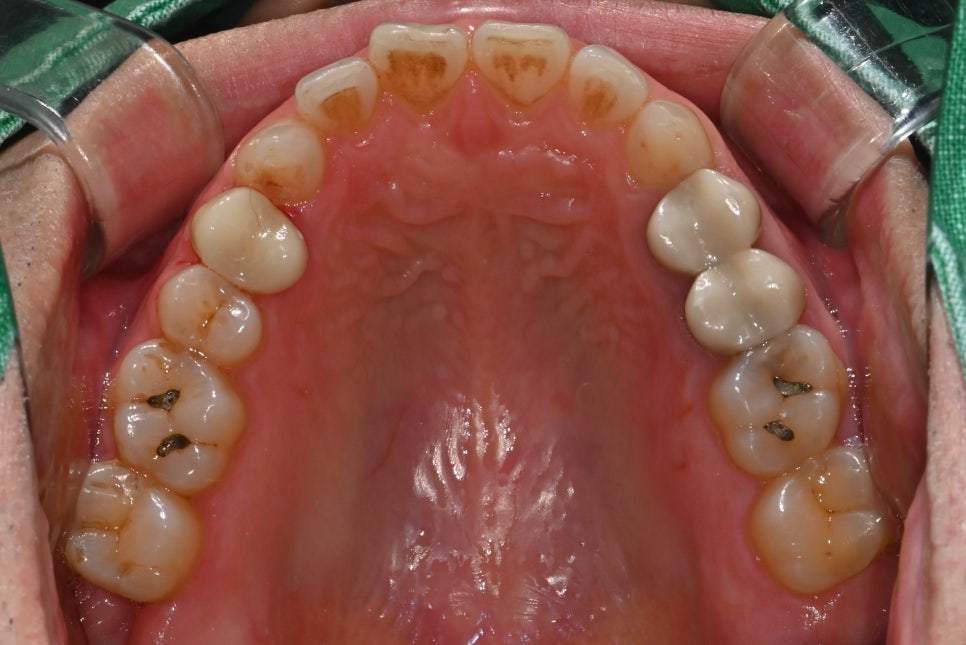

Second photo: Upper molar photo taken at the initial visit. The caries area and the broken tooth condition are visible.

Third photo: Lower molar photo taken at the initial visit. Caries had progressed in two lower molars, and inlay treatment was needed.